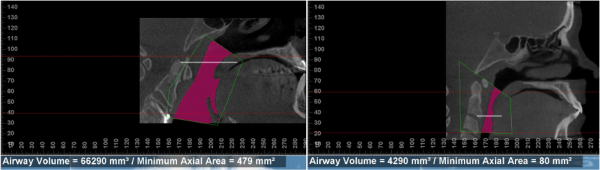

The purple zone is the airway of two different people. The one on the left has a total volume of about 66,000 mm, while the one on the right has a volume of about 4,000 mm.

If these two people go running down a field, which one do you think will run longer and faster.

Who do you think will be huffing and puffing sooner?

If they both get some mucus in their airway, who do you think will be told they need an inhaler to breathe easier?

Who do you think is more likely to mouth breathe and begin getting allergies first?

Who do you think sleeps better? Gets headaches? Has TMJ? Has migraines? Has sleep apnea? Will live healthier and longer?

What kind of airway would you like to have for yourself and your loved ones?